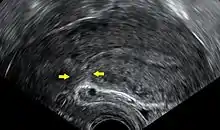

Transvaginal ultrasonography of a uterus years after a caesarean section, showing the characteristic scar formation in its anterior part

A caesarean section is associated with risks of postoperative adhesions, incisional hernias (which may require surgical correction), and wound infections.[20] If a caesarean is performed in an emergency, the risk of the surgery may be increased due to a number of factors. The patient's stomach may not be empty, increasing the risk of anaesthesia.[21] Other risks include severe blood loss (which may require a blood transfusion) and post-dural-puncture spinal- headaches.[20]